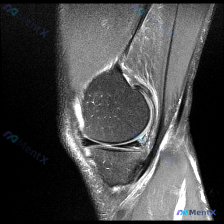

问题:临床怀疑存在半月板异常,仅提供单张膝关节MRI-T2序列矢状位影像,请给出影像判断和分析。

这张影像的情况是:

- 骨结构:股骨远端、胫骨近端、髌骨皮质轮廓完整,骨髓信号均匀,没有骨折、骨挫伤、骨质破坏或者骨赘增生

- 半月板:前角后角形态正常,T2序列是均匀低信号,没有看到线状/带状高信号穿透关节面,连续性完好,没有明确撕裂征象

- 韧带肌腱:后交叉韧带完整,走行信号正常;前交叉韧带、髌腱也没有看到明显连续性中断或者信号异常

- 关节与软组织:只有少量生理性关节积液,髌下脂肪垫信号均匀,周围软组织没有异常占位或水肿